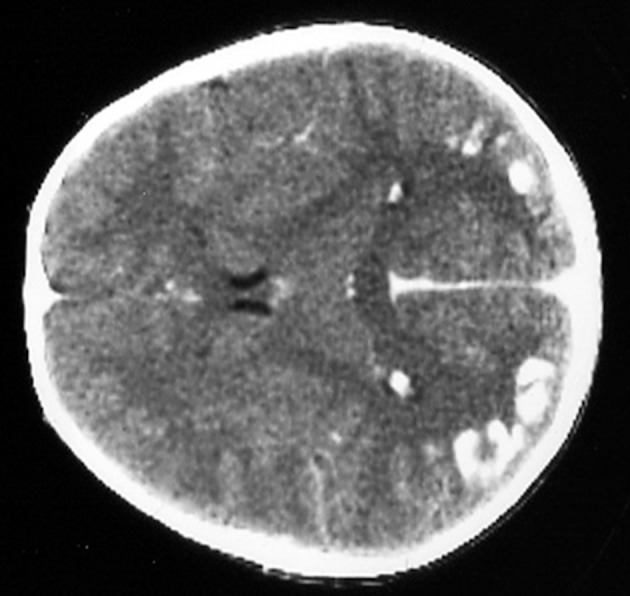

Several neurological manifestations are significantly associated with CD in the pediatric population. The most common being headache, that is present in up to one-fifth of the cases. Rarer conditions in the pediatric population are ataxia and neuropathy, ranging from 0.1 to 7.4%. A prevalence of 0.7–2%, not significantly different from the general population, has been described in some studies (59, 60), however other authors reported a 1.4 fold increase of epilepsy in CD children (61, 62). Thus, the link between epilepsy and CD remains still uncertain. The most common seizures patterns are the complex partial, followed by tonic-clonic seizures. A particular type of epilepsy characterized by the presence of occipital calcifications has been specifically reported in association to CD (63, 64)—Figure 1.

Figure 1.

Bilateral occipital calcifications in celiac disease.